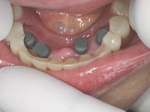

術前(下顎粘膜面、鏡像)

4本埋入終了(このシステムは4本が絶対条件)